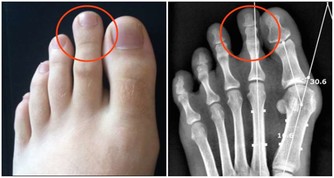

讓我們先來回想一下,靜脈曲張的形成原因主要有哪兩個?一是先天性的血管壁薄弱,這一點我們沒法干預;另外一個原因是久坐久站,姿勢不正確。這個是完全可以改正的。因此,避免靜脈曲張的關鍵就是避免久站久坐。